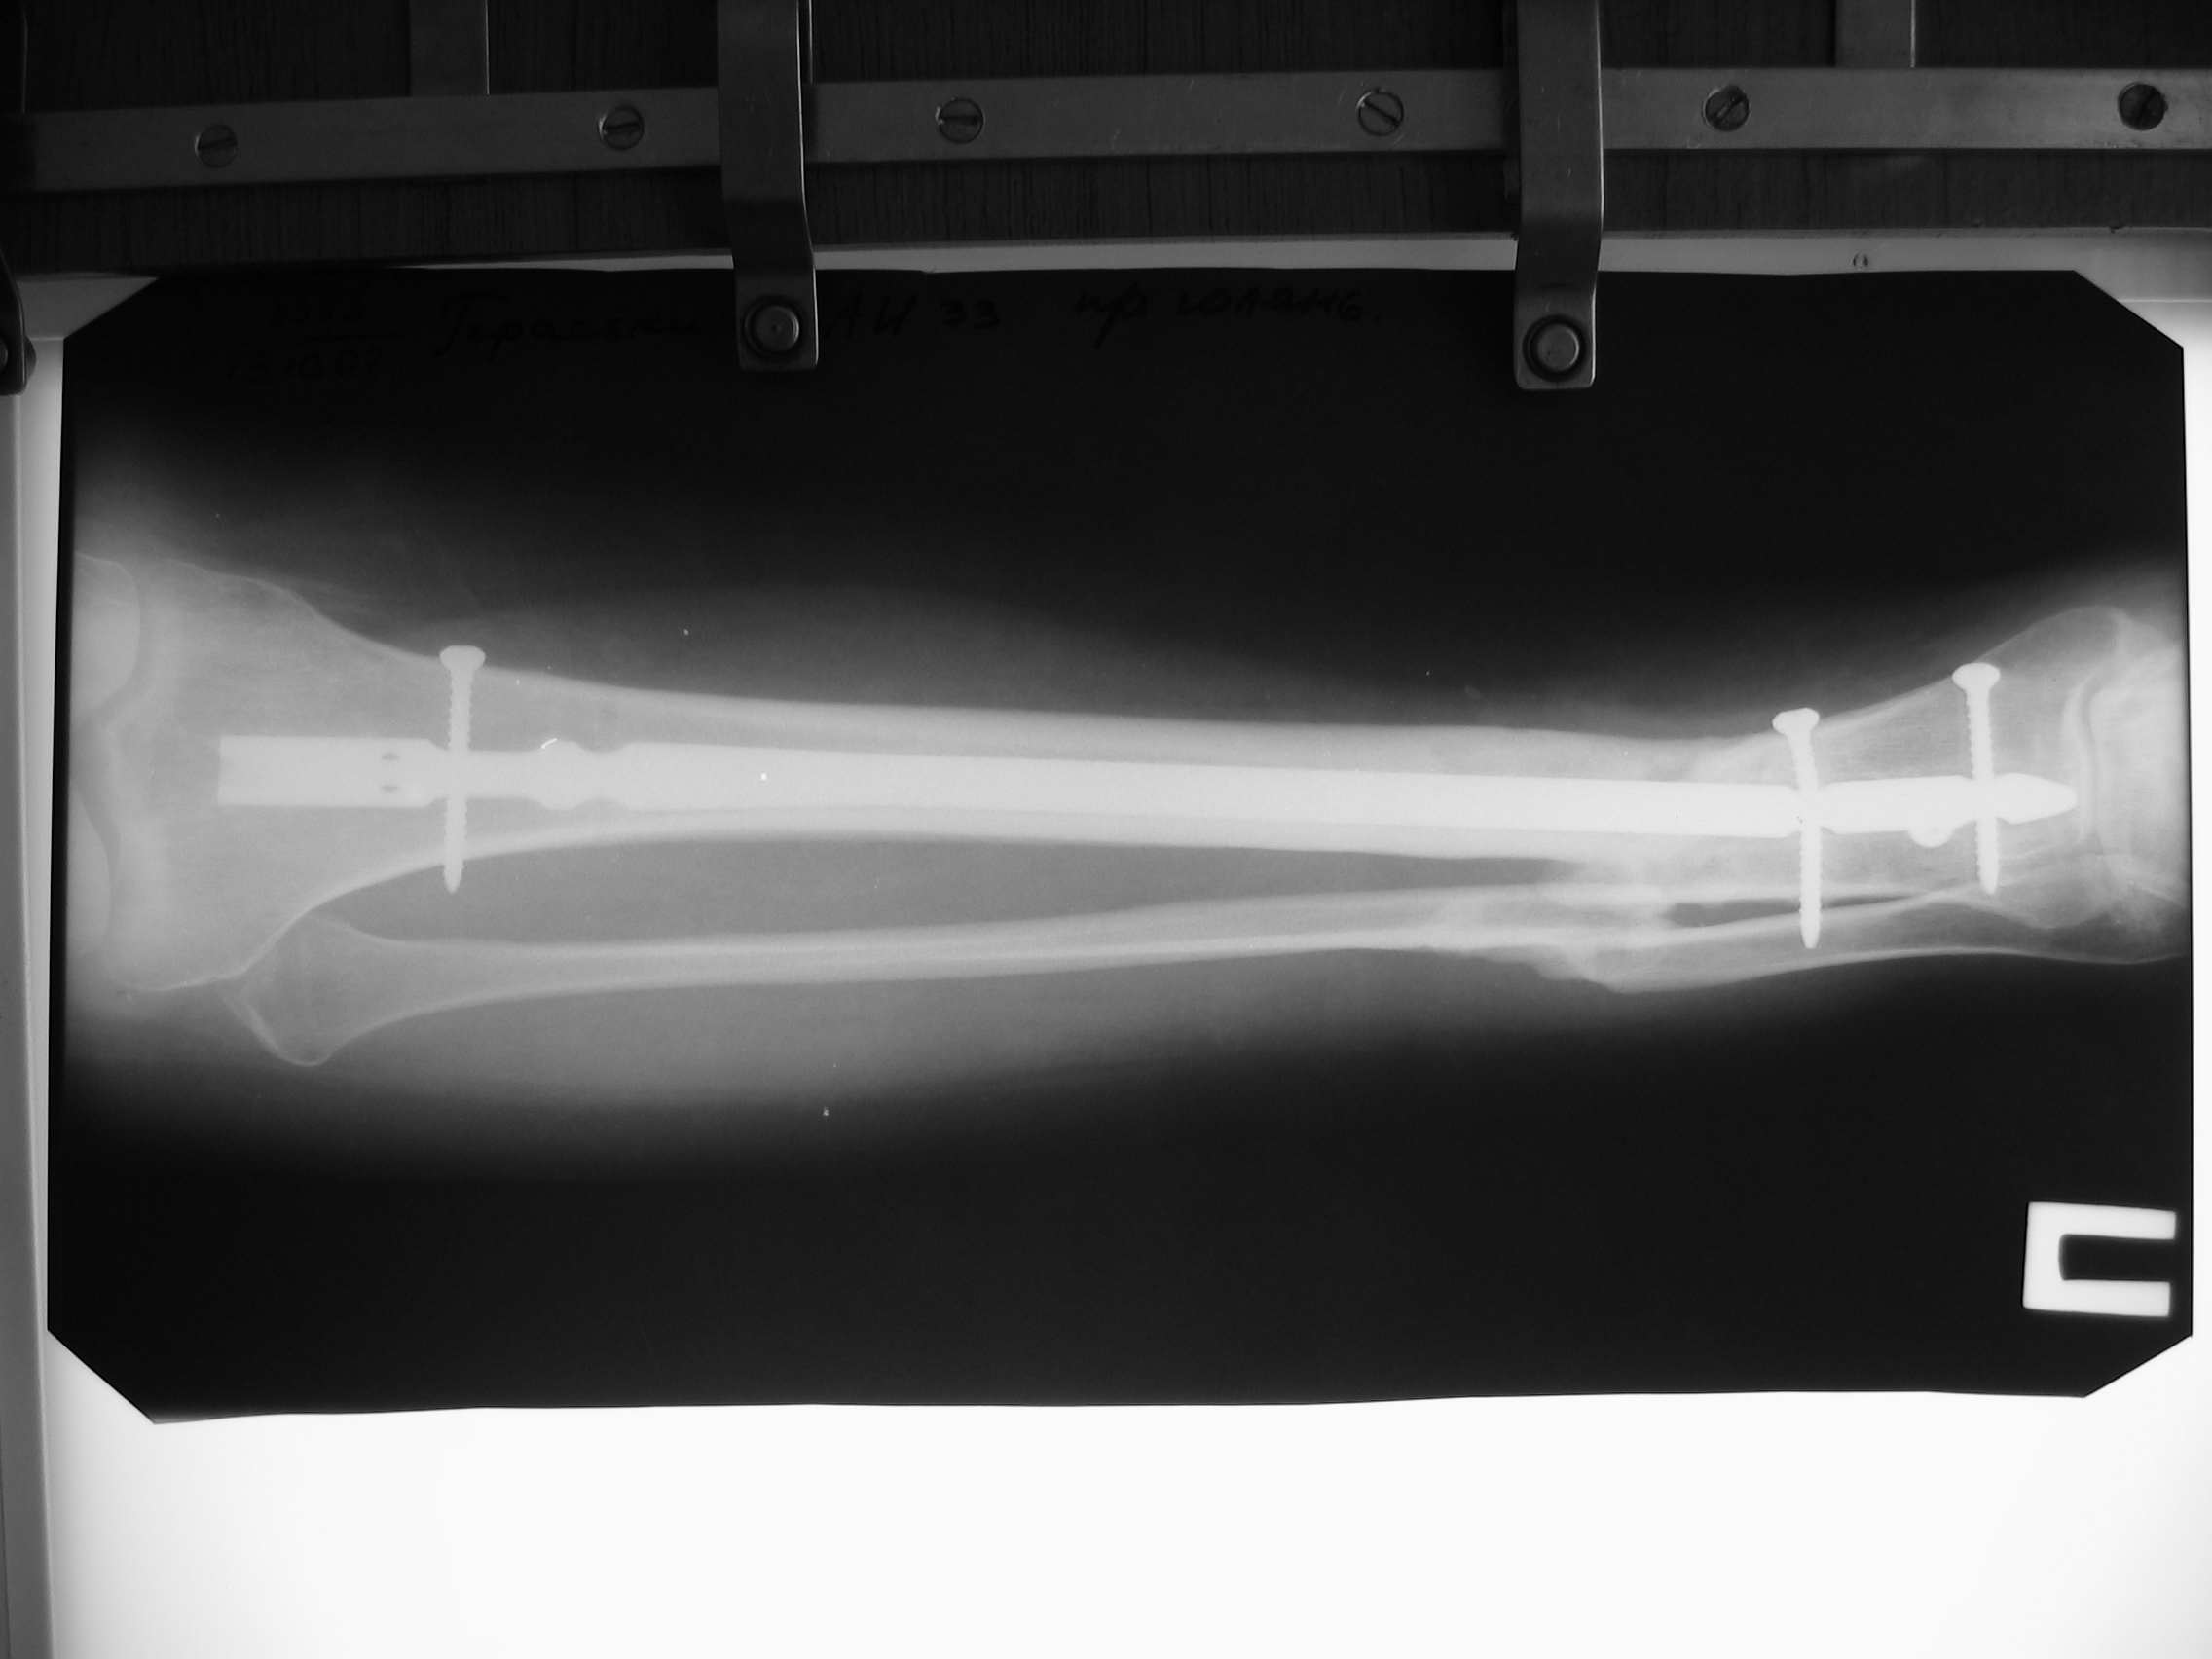

[Ortho] Ложный сустав голени перелом штифта

маленькие тех проблемы, высылаю снимки